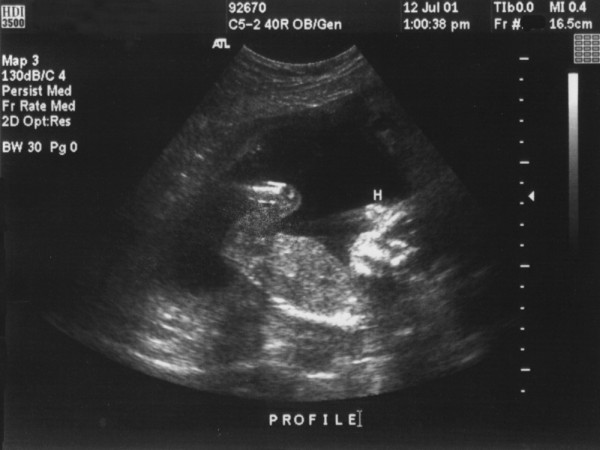

УЗИ

Узнать о состоянии на 14-й акушерской неделе беременности можно с помощью ультразвукового исследования. Если беременность протекает без осложнений, УЗИ не требуется. Однако при выявлении патологий или угрозы ультразвуковое обследование становится обязательным.

Во время процедуры специалист оценивает:

- размеры и массу плода;

- место прикрепления к плаценте;

- размеры воротниковой зоны;

- расположение внутренних органов и структуру головного мозга.

Половые органы плода завершают формирование, и врач может предположить пол ребенка, если плод находится в правильном положении – головой вниз.